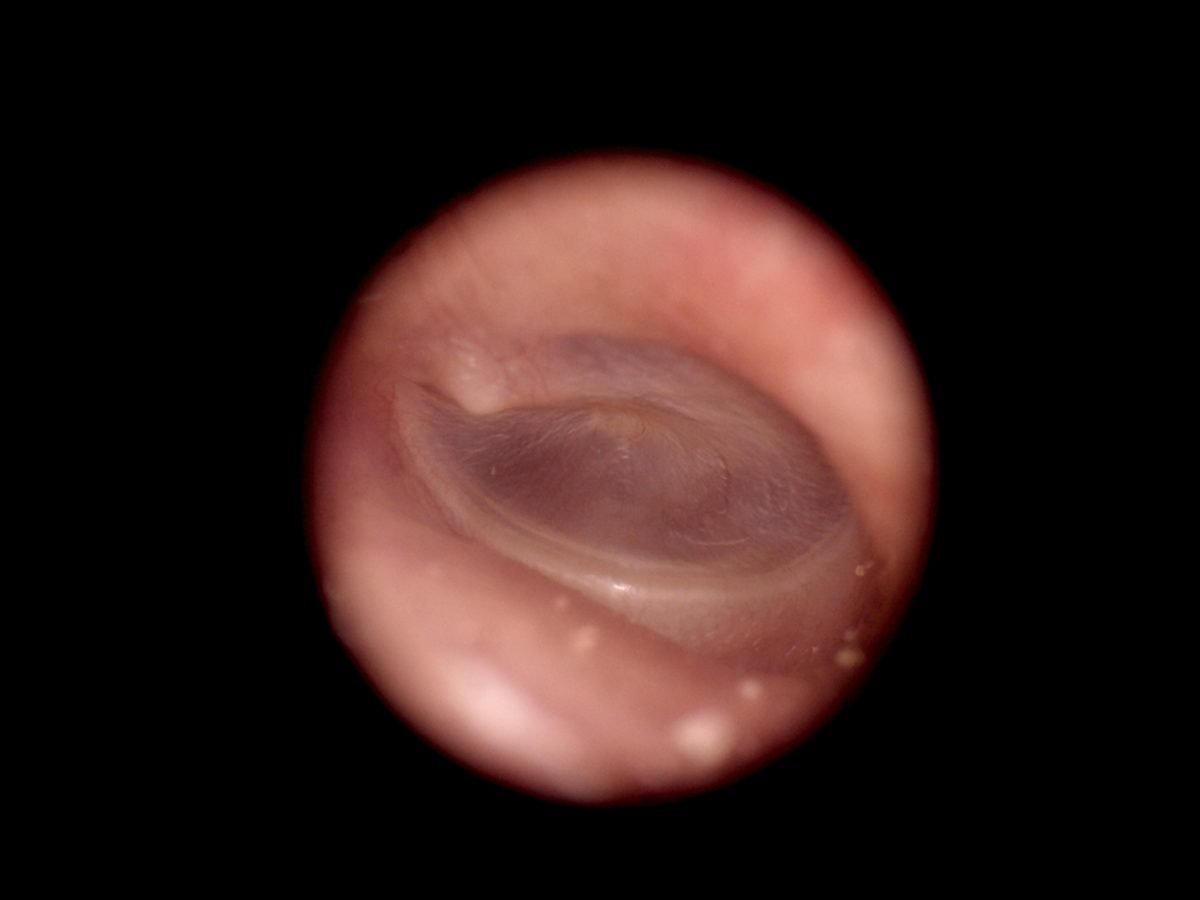

- Provide high definition clinical image

- Portable and hand held application in disease screen

- Multi functional diagnosis in ophthalmology , ENT . Dermatology and general practice.

Image Gallery

Through the scope